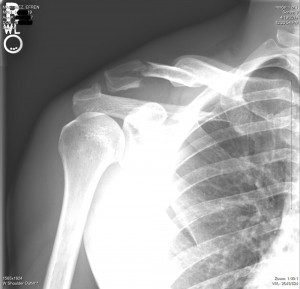

Efrens-Broken-ClavicleMV